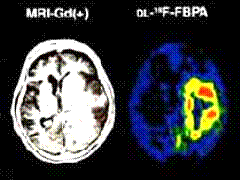

Глиобластома Астроцитома

Рисунок 18 - Диагностика опухолей головного

мозга